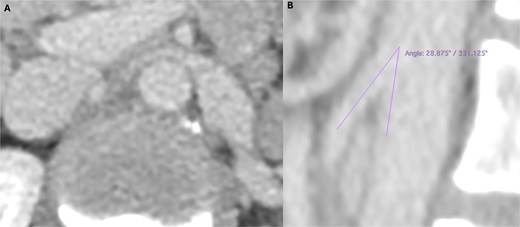

Lab tests showed microscopic haematuria (>0.45 × 106/l). Doppler ultrasound revealed LRV compression, with a diameter reduction from 12.5 to 1.5 mm, and a peak systolic velocity increase from 34 to 160 cm/s (velocity ratio > 4). CT angiography (Fig. 1) confirmed an aortomesenteric angle of 28° and ectasia of the left ovarian vein (9 mm).

Preoperative computed tomography angiography demonstrating compression of the left renal vein in axial section (A) and sagittal section (B), revealing an aortomesenteric angle of 28°.